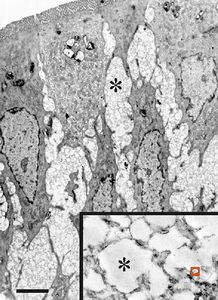

M,35y. | duodenum … lipid malabsorption - susp. hypo-beta-lipoproteinemia